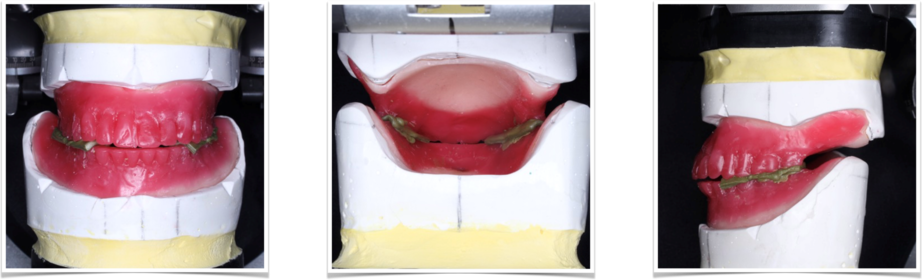

入れ歯(義歯)の写真

下顎にシリコンがしかれています。このシリコンに問題があるのでは?と目が行きがちですが、実際は入れ歯(義歯)の人工歯がかなり削れてしまっている事がわかりました。人工の歯が削れている為、噛んだ際に入れ歯(義歯)が安定しません。

この入れ歯の歯が、なぜこんなに削れてしまったのでしょうか?顎の位置がずれているのでしょうか?噛む位置がズレているのでしょうか?様々な問題が考えられます。

そのため、シリコンを入れ歯(義歯)の裏側に単につけたからといって、入れ歯(義歯)が痛くなく噛めるかといえば、そうは上手く行きません。

という事で、基本に戻って今の入れ歯の問題点を解決するべく、治療用義歯を作製して最後入れ歯(義歯)を作ることにしました。

かみ合わせ

今回は、コピー咬合床と言われる特殊なかみ合わせを採る装置を作製しました。コピー咬合床の良いところは、足したり引いたりする事が、簡単に出来るところです。

また、以前の入れ歯(義歯)を参考に出来る点も良い点です。

ゴシックアーチ

入れ歯(義歯)に詳しい歯科医師ならば、必ずこの呼び名を聞いたことがあるはずです。やった事がある・ないは、歯科医師の師事した先生によるのかも知れません。

私は、かみ合わせの水平的な位置を確認するために良く用います。

ピエゾグラフィー

入れ歯(義歯)の歯をどこに並べたら良いか?特に歯の無い症例ですと迷うことが多くなります。

私が2代目に教わった方法は、元天然の歯があった位置に入れ歯(義歯)の歯を並べなさいでした。この元歯のあった位置を再現することができる方法が、ピエゾグラフィーになります。